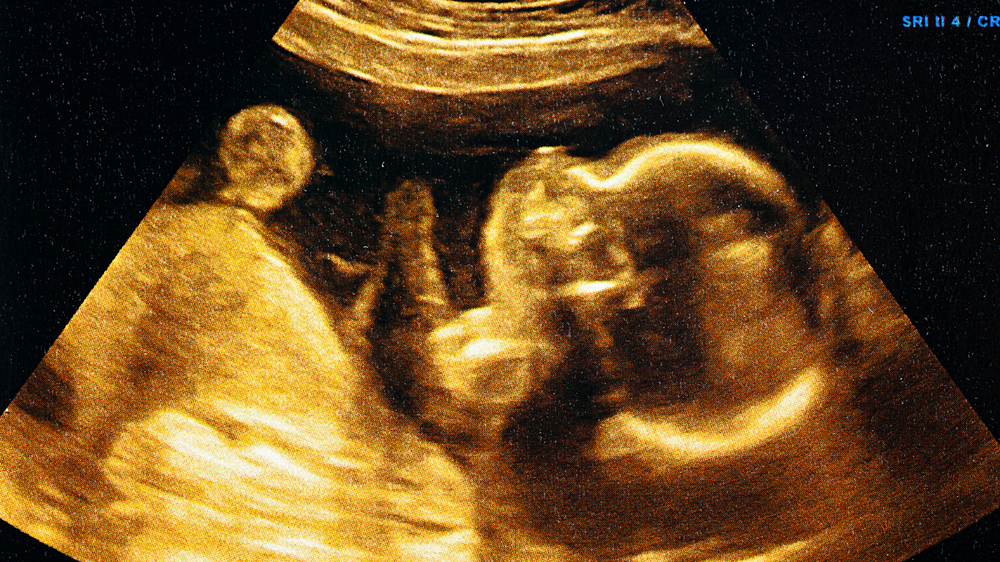

Regular sonography and growth measurements can be performed, during which physicians monitor the baby's development, particularly skin and fat formation.

3. Can a sonography detect changes in a baby’s skin?

A sonogram cannot directly show how thick the baby’s skin is. It’s useful for evaluating fat deposits and how well the baby is growing.